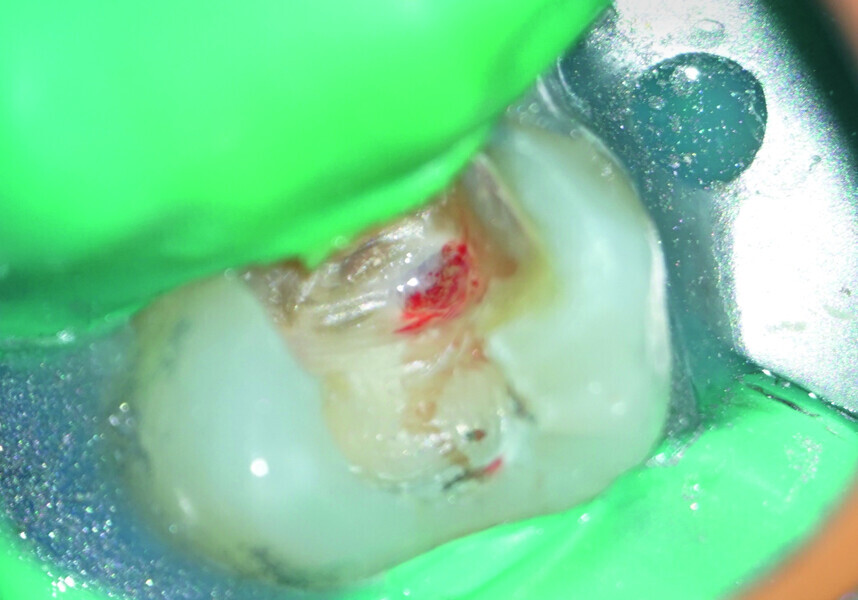

Direct pulp capping as a conservative procedure to maintain pulp vitality